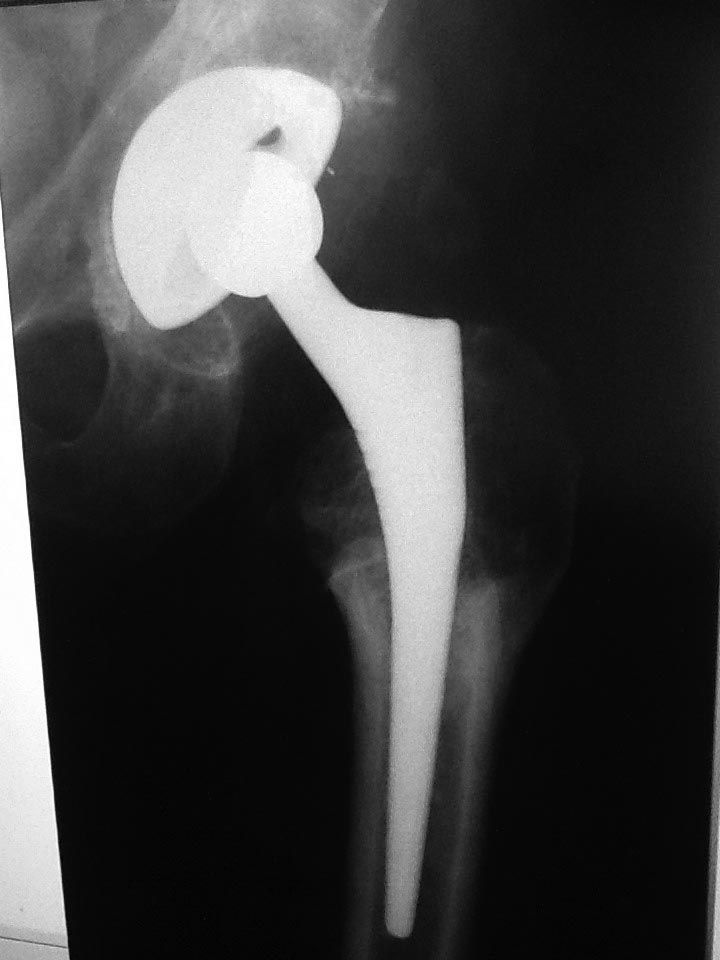

прямая проекция